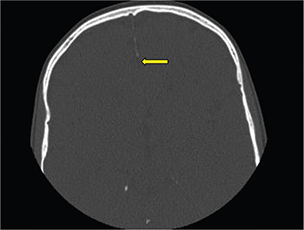

As part of the workup for the dental findings, she had a computed tomography (CT) of the head, which identified a calcified falx cerebri (Figure 2). A CT of the jaw (Figure 3) revealed multiple mini cysts and a large cyst in her lower jaw. Surgery removed a cyst from the right mandibular body and ramus associated with impacted tooth #31 pathology was consistent with an odontogenic keratocyst. After being seen by the surgeon, she was referred for genetic testing. Her past medical history was notable for a broken arm, benign hydrocephalus at around 8 months of age for which she had magnetic resonance imaging performed.

Fig. 2. Axial head CT of 11-year-old female showing calcifications of the falx cerebri not typically present at this age. CT: computed tomography.